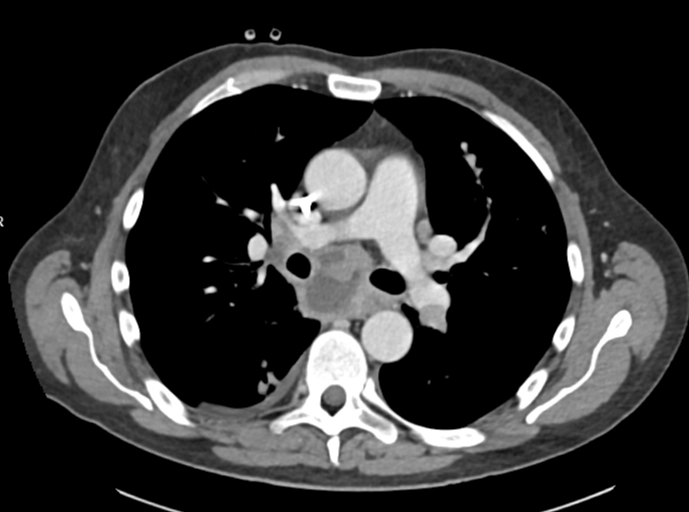

Di căn theo đường máu (Hematogenous Metastases)

16/03/2026